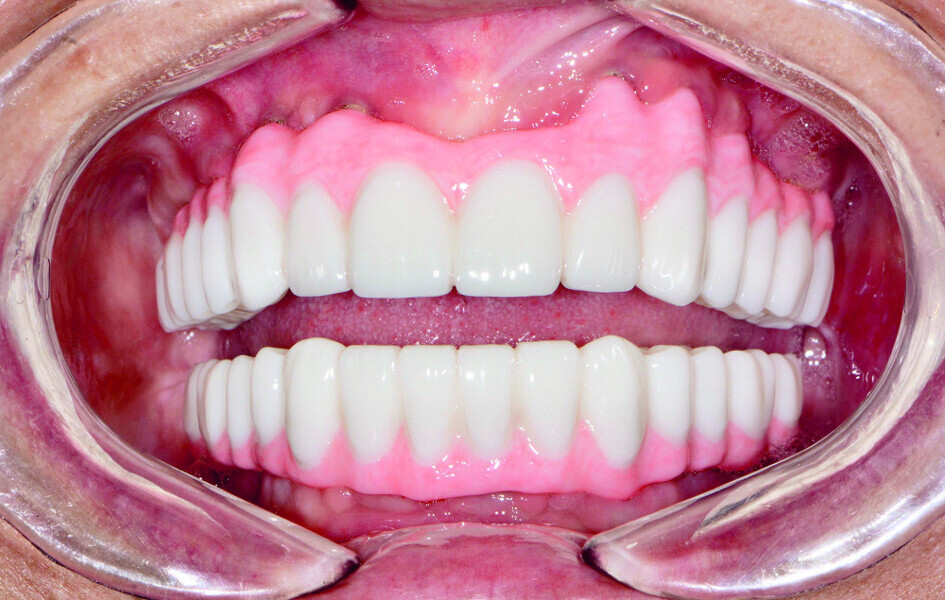

Fig 20 Composant du sourire en PMMA

Fig 21 Vue des dents non engrenées